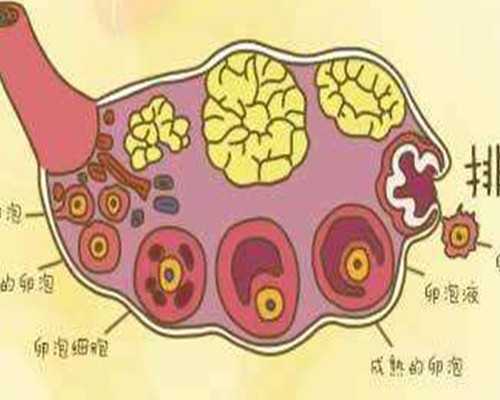

45歲之后,很多女性都處于圍絕經(jīng)期,卵巢內(nèi)可以利用的卵子很少。同時,隨著年齡增加,卵子質(zhì)量下降,受精后,發(fā)生染色體異常分裂的概率大大增加,相應(yīng)的,染色體異常的胚胎生成增加。數(shù)量和質(zhì)量都下降的情況下,胚胎著床率大大下降,臨床妊娠率<5%,接近為0,即使懷孕,出現(xiàn)胚胎停育的風(fēng)險也大大增加。

贈卵試管嬰兒治療技術(shù)能解決這種困境嗎?確實是一個途徑。然而,贈卵可遇不可求,這樣的機會特別少。贈卵來源于因為不孕癥行試管嬰兒治療的不孕女性,當(dāng)她促排卵后獲卵數(shù)很多,且自愿貢獻出一部分卵子時,才能實現(xiàn)。盡管采取的是雙盲贈受,即兩對夫婦分別不知卵子來源或去向,但可能今后也會面臨某些倫理問題。